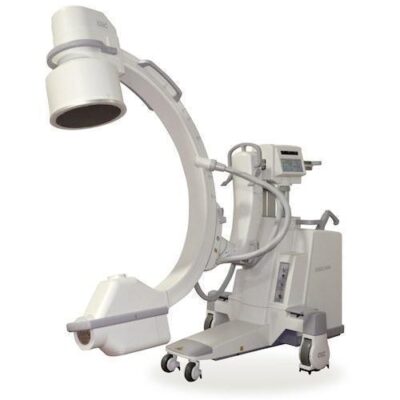

Système de Radiographie Numérique Mobile

Découvrez le système de radiographie numérique mobile PLX5500 65 kW : imagerie haute puissance, exposition ultra rapide 1 ms et faible fuite de rayonnement. Solution idéale pour hôpitaux au Maroc.

Le PLX5500 est un système de radiographie numérique mobile haute performance conçu pour offrir une imagerie rapide, précise et sécurisée directement au chevet du patient.

Grâce à sa puissance de 65 kW, il garantit des images claires et détaillées pour tous types de patients, tout en réduisant les déplacements vers la salle de radiologie.

✔ Générateur haute puissance 65 kW

✔ Exposition ultra rapide 1 milliseconde

✔ Images nettes pour patients de toutes tailles

✔ Faible fuite de rayonnement

✔ Idéal pour soins intensifs et urgences